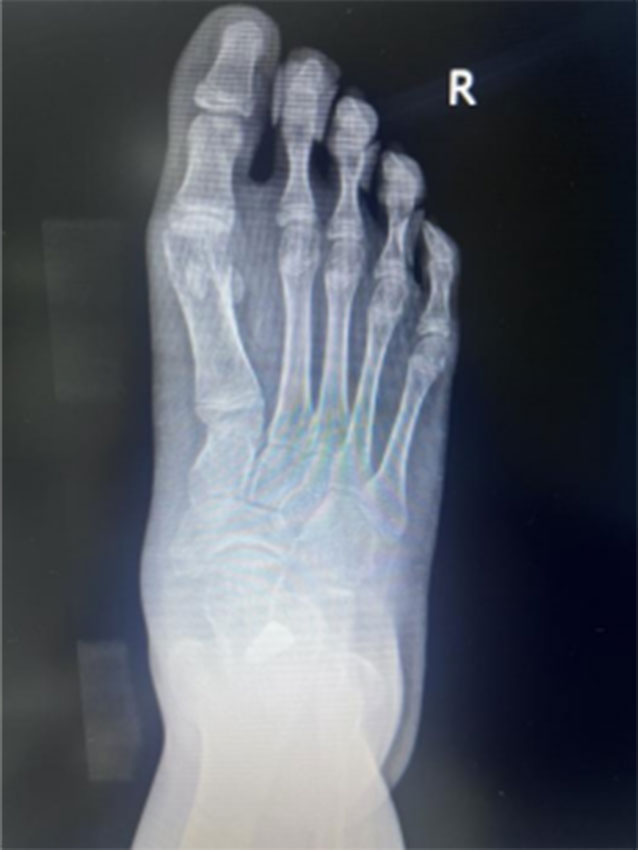

2024年6月13日,西南医科大学附属中医医院骨伤科关节·足踝组张磊博士门诊接诊了一名扁平足的初中生。14岁的小莉走路过程中足底有疼痛感,长时间走路后会感觉足底肿胀,遂来医院就诊,被诊断为“右足副舟骨痛+右足扁平足”,张磊博士团队考虑小莉实际情况,经微创治疗距下关节制动术后,小莉疼痛症状缓解。

12月1日,小莉再次来到骨伤科关节·足踝组复查,外观可见扁平足改善效果明显。

扁平足是青少年较为常见的足踝疾病,以足纵弓降低或消失为主要特征,该病症患者负重力线不正常,发展到一定程度可能会出现足部疲劳或疼痛症状,一般可分为可复性扁平足(柔韧性平足)和僵硬性扁平足。